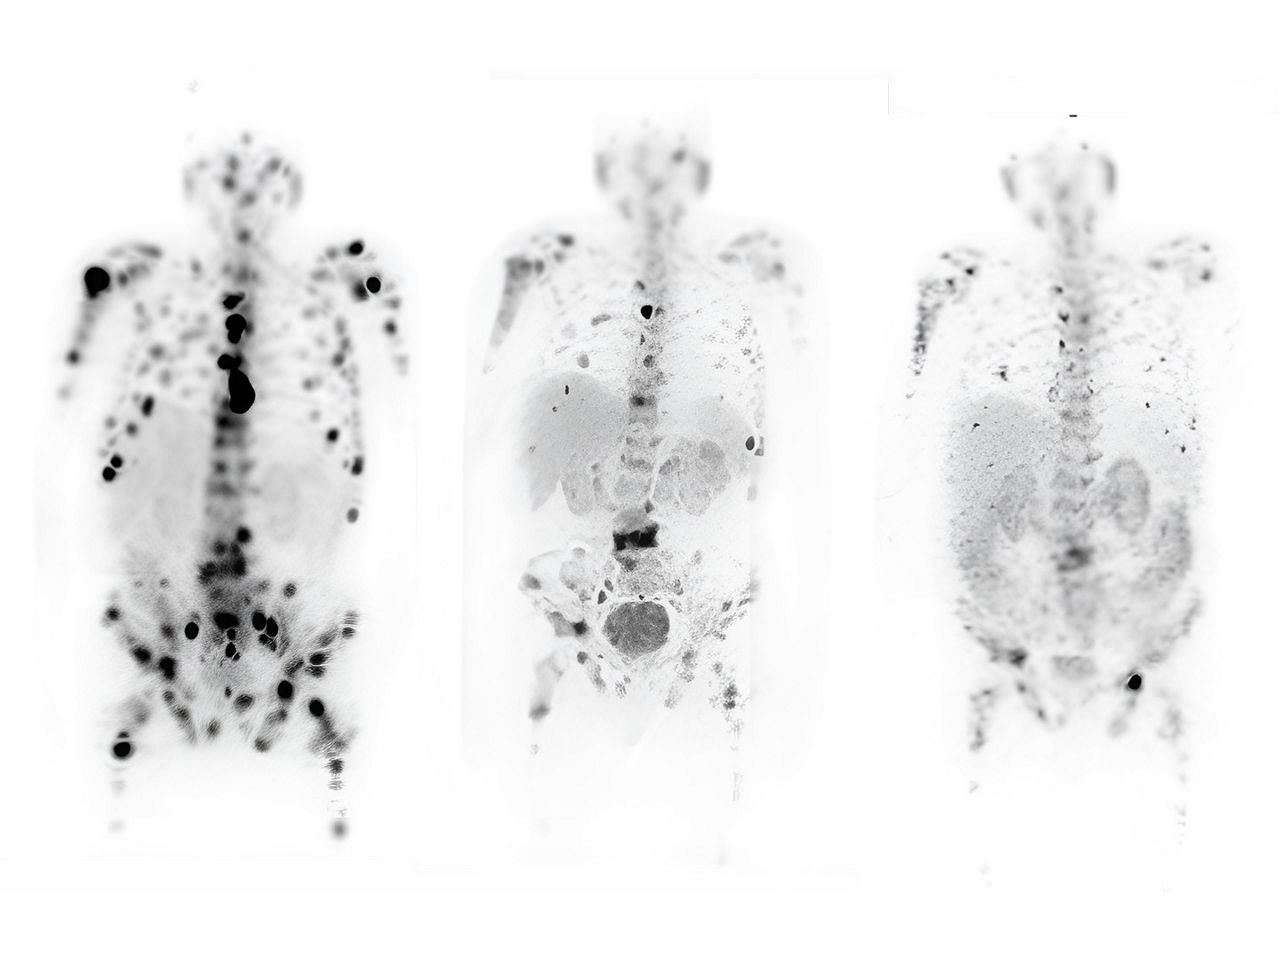

Theranostics is an exciting field of molecular medicine. Enabled by molecular imaging techniques such as positron emission tomography (PET) and single photon emission tomography (SPECT), the theranostic approach uses specific targeting compounds for both imaging and therapy of a particular malignancy. Its ability to identify areas of disease that are more likely to respond to targeted therapies is invaluable to cancer patients. And clinicians are praising its successes and its potential to help them more effectively navigate disease management by aligning patients with the treatments that will be most impactful for them.

With the evolution of advanced imaging technologies, and the continuous search to discover new tracers for targeted therapies, industry leaders such as GE Healthcare are fortifying the entire molecular imaging pathway, from providing access to emerging molecules to continuing to push the limits of molecular imaging with PET/computed tomography (CT) and SPECT/CT technologies. Innovations in molecular imaging technology introduce much more imaging data for processing and include highly sophisticated automated tools and artificial intelligence (AI)-based reconstruction algorithms to assist clinicians as they render complex diagnoses. Molecular imaging is essential in theranostics, allowing for non-invasive, repetitive assessment of the compound uptake and allowing for characterization of the tumor tissue, and therapy response over time.

The reliance on molecular imaging techniques such as PET/CT and SPECT/CT to provide clinicians quantitative data about metabolic tumor characterization, combined with knowledgeable clinicians to acquire, interpret and monitor treatment effectiveness are the keys to the future of and potential for theranostics to become standard of care. PET imaging, for example, can interrogate the whole body for the expression of therapeutic targets.10 The presence and degree of target expression are associated with a therapy response. Thus, PET imaging probes have been introduced as predictive biomarkers.11